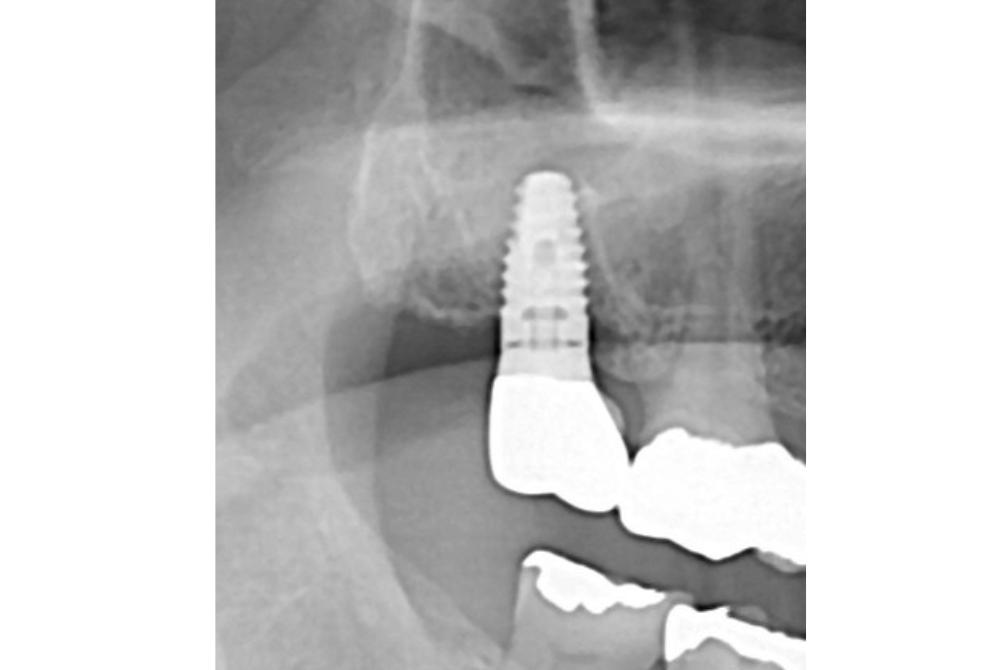

年齢・性別55歳・女性 部位左上7番

治療内容 歯根破折により抜歯済みの歯に、インプラントを埋入。

治療方法 CTおよびパントモレントゲンからインプラントの埋入位置を計測し、麻酔下にてインプラントを植立。 仮歯を入れて約3か月待機後、セレック治療にてジルコニアクラウンを製作し、同日装着。

治療結果 噛める歯が増えて、噛みやすくなる。

費用 ・左上7番 インプラント埋入:220,000円

・(約3か月後)被せ物作成:ジルコニア 110,000円